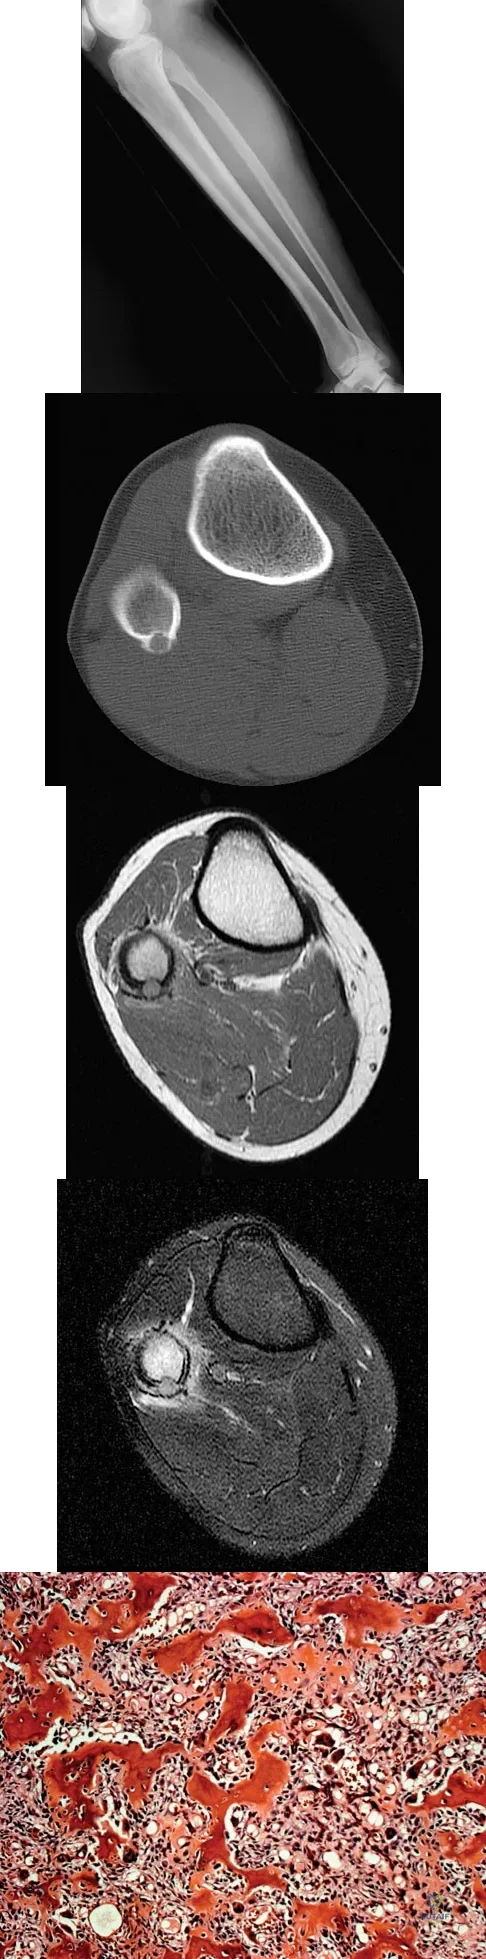

Question 1

A 23-year-old man has had right posterolateral knee pain and occasional lateral calf dysesthesias for the past 8 months. A radiograph, CT scan, MRI scans, and a biopsy specimen are shown in Figures 62a through 62e. What is the most likely diagnosis?

Explanation